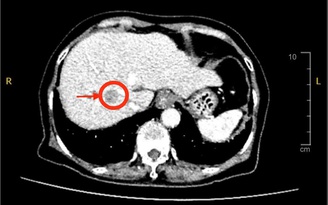

Liệu có thể giảm mỡ trong gan chỉ với một loại thức uống?